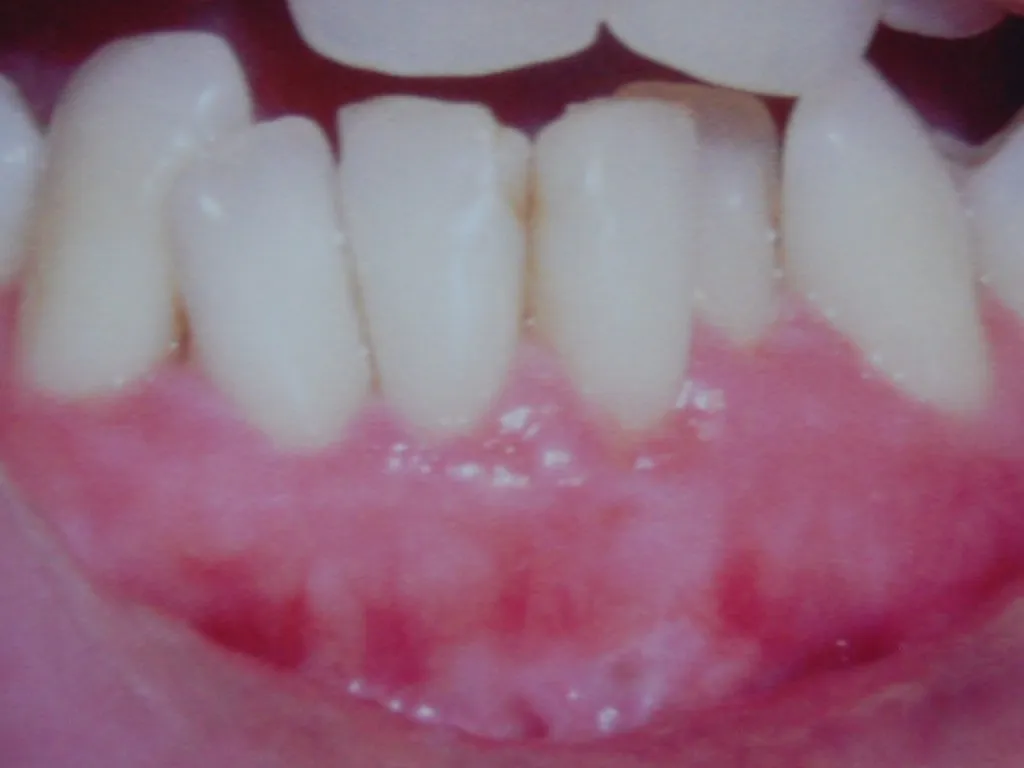

Guided Tissue Regeneration with Bone Graft & Growth Factors to Save teeth